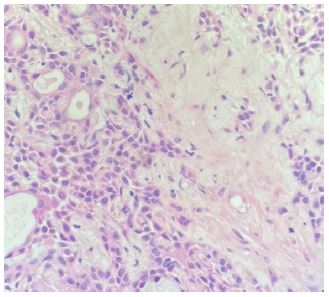

On physical exam, the patient showed normal external nasal landmarks. Anterior rhinoscopy showed intact but deviated nasal septum, and a tan yellowish mass adjacent to the nasal septum with some mucopurulence. Maxillofacial Computed Tomography (CT) scan showed a homogenous 14 mm by 18 mm left anterior nasal cavity mass involving the anterior aspect of inferior turbinate with mass effect on the nasal septum (Figure 1). The patient was then consented and underwent excision of the left nasal mass with concurrent septoplasty and inferior turbinate submucosal resection. Intraoperatively, the mass was found to be solid in consistency, and was removed in piecemeal fashion to gross total resection. During the post operative period, office nasal endoscopy showed irregular mucosal tissue along the anterior inferior turbinate and nasal floor concerning for residual disease. The patient was then referred to tertiary care for complete excision. Additional resection was performed including partial resection of the inferior turbinate and mucosa lining the anterior inferior nasal septum and nasal floor. Further follow-up 12 months post operatively showed no residual disease or recurrence.

Figure 1: Representative images of coronal (a) and axial (b) Computed Tomography (CT) with contrast Left anterior nasal cavity mass involving anterior inferior turbinate with extension to nasal floor and nasal septum. No gross bony changes.